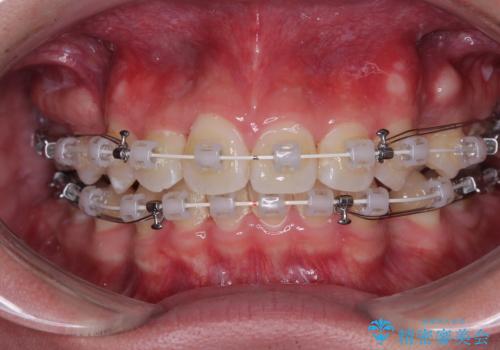

- 矯正装置

- 審美装置

矯正装置には白いプラスチックブラケットと白いコーティングワイヤーを使用し、見た目にも配慮した治療を行いました。